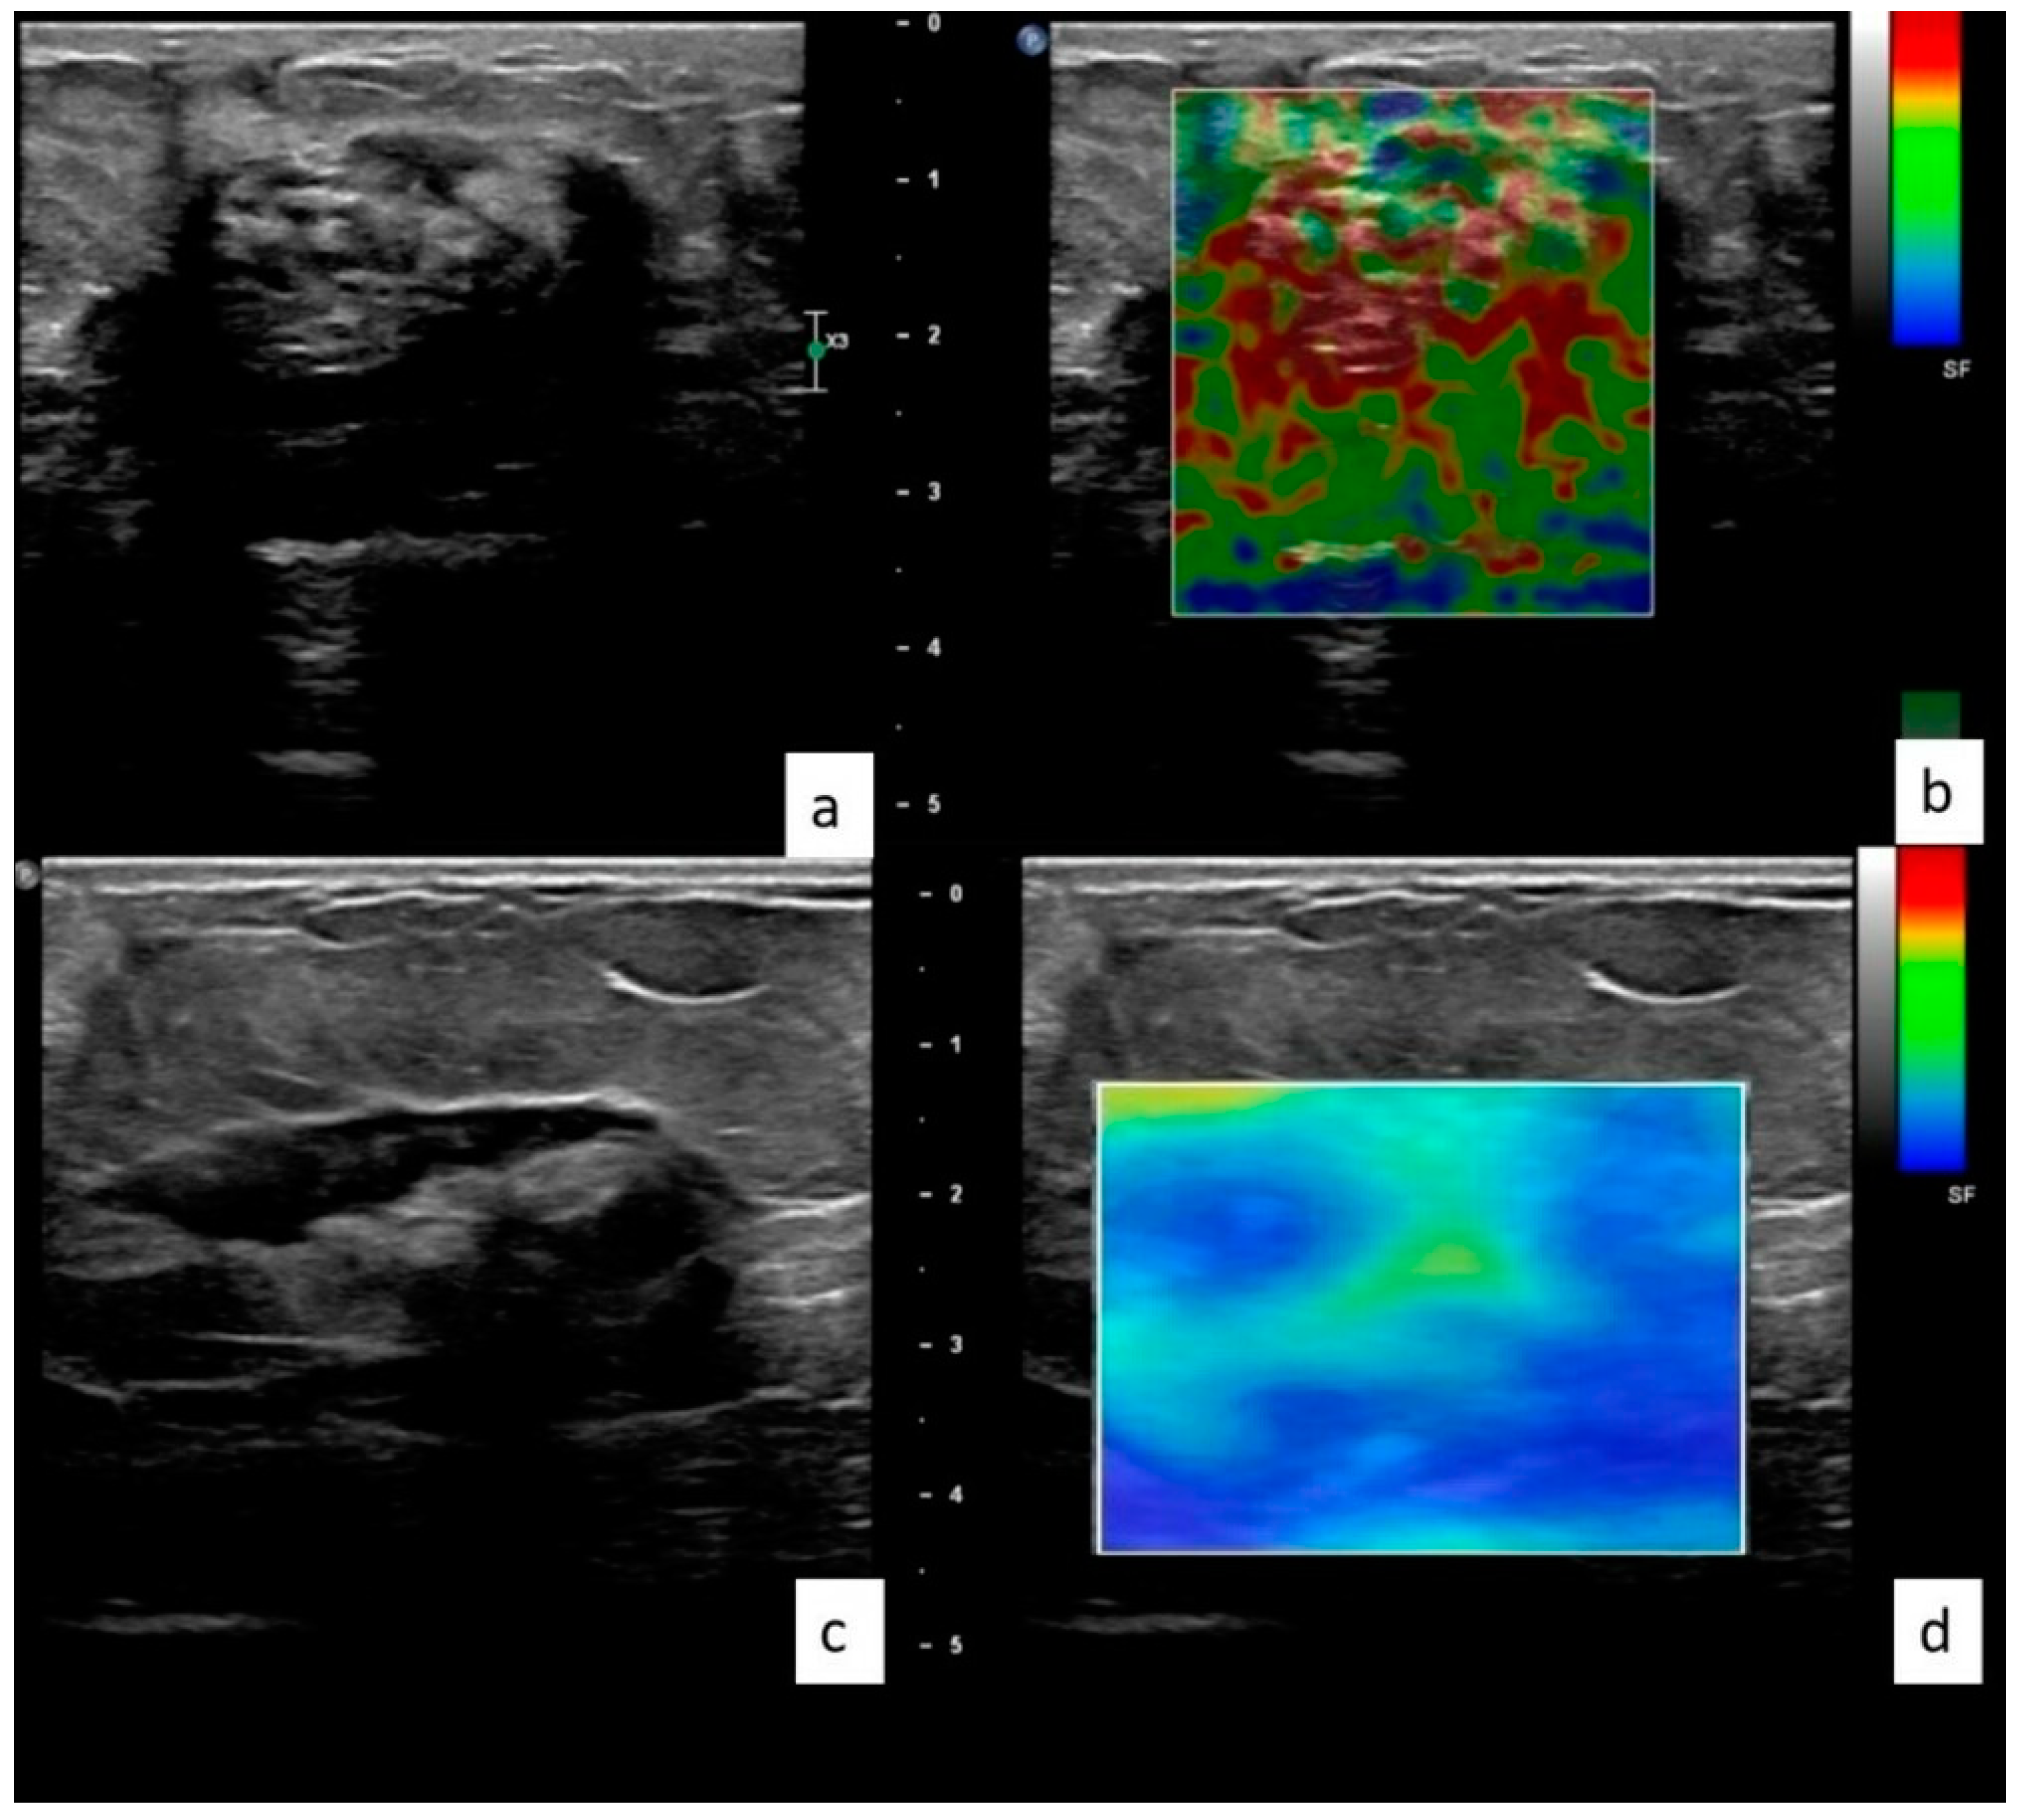

Figure 2. 38 year old female with pathologically confirmed granulomatous mastitis. The lesion was located on the right breast, upper quadrant. The patient was treated locally. Elastographic examinations at the time of diagnosis (a,b) and 8 weeks after treatment (c,d) reveal that the lesion’s elasticity value (kPa) decreased by 57.9%, from 77.5 to 32.6 kPa.